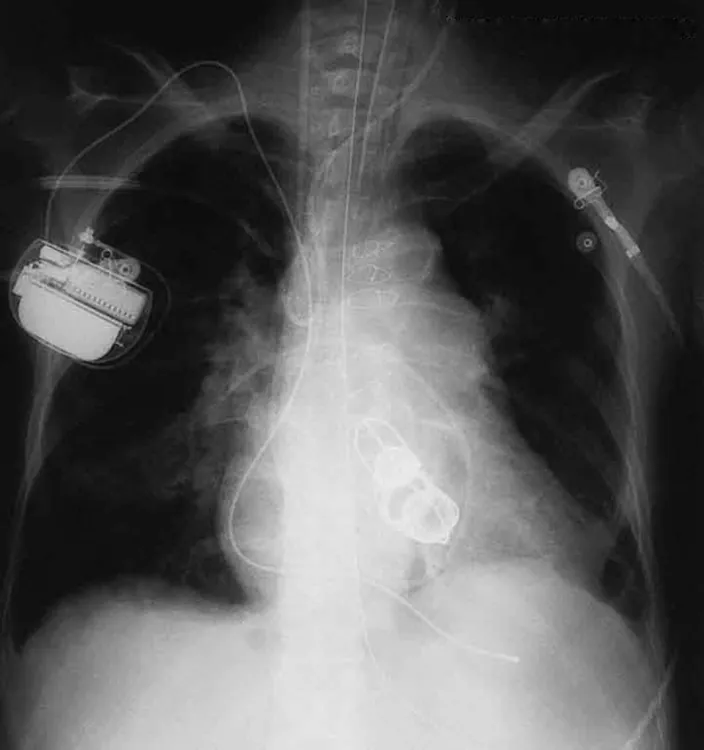

The ability of X-rays to penetrate matter depends on density, and so an X-ray image can reveal very detailed density information. Figure 24.21 shows an example of the simplest type of X-ray image, an X-ray shadow on film. The amount of information in a simple X-ray image is impressive, but more sophisticated techniques, such as CT scans, can reveal three-dimensional information with details smaller than a millimeter.

An X ray image of the chest is shown. It shows the section of the heart with artificial heart valves, a pacemaker, and the wires used to close the sternum.

Figure 24.21 This shadow X-ray image shows many interesting features, such as artificial heart valves, a pacemaker, and the wires used to close the sternum. (credit: P. P. Urone)